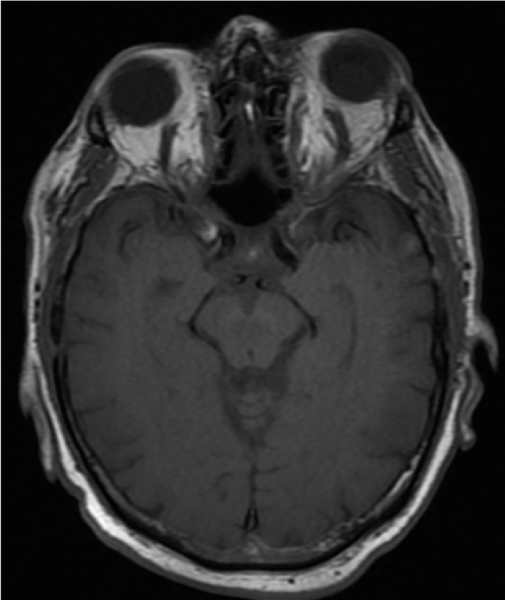

T2 MRI demonstrating bilateral superior ophthalmic vein enlargement

| current | 08:51, March 26, 2020 | 700 × 831 (313 KB) | Jacquelyn.Laplant (talk | contribs) | T2 MRI demonstrating bilateral superior ophthalmic vein enlargement |